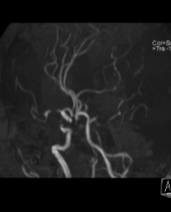

神经介入诊疗中心主任、副主任医师刘俊中接诊后,根据各项检查检验结果迅速判断张女士属于颅内大血管病变。

左侧大脑中动脉和颈内动脉均已闭塞,相当于左侧大脑半球几乎断了供血,手术指征明确。

5 分钟后,张女士被推进介入手术室,急诊脑血管造影进一步确认了血管闭塞情况。

10 分钟后,手术顺利完成,堵塞血管成功开通,濒临坏死的脑细胞被及时 “救回”,张女士的病情得到了有效控制。